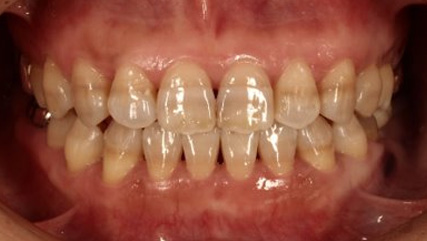

治療前

治療終了前

上顎前突といわれ、上顎の前歯が唇側に出ている状態を言います。

前歯が出ることで見た目の問題もありますが、口を閉じることができない、口呼吸をしてしまう、外傷などのリスクがあります。

日本人に叢生の次に多い不正咬合と言われており、自然に治ることはありません。また上の前歯が出ている事だけが気になるかもしれませんが、多くの場合、上顎の奥歯の位置に問題があることが多く、部分矯正でなく根本的な治療をした方がいい場合が殆どです。